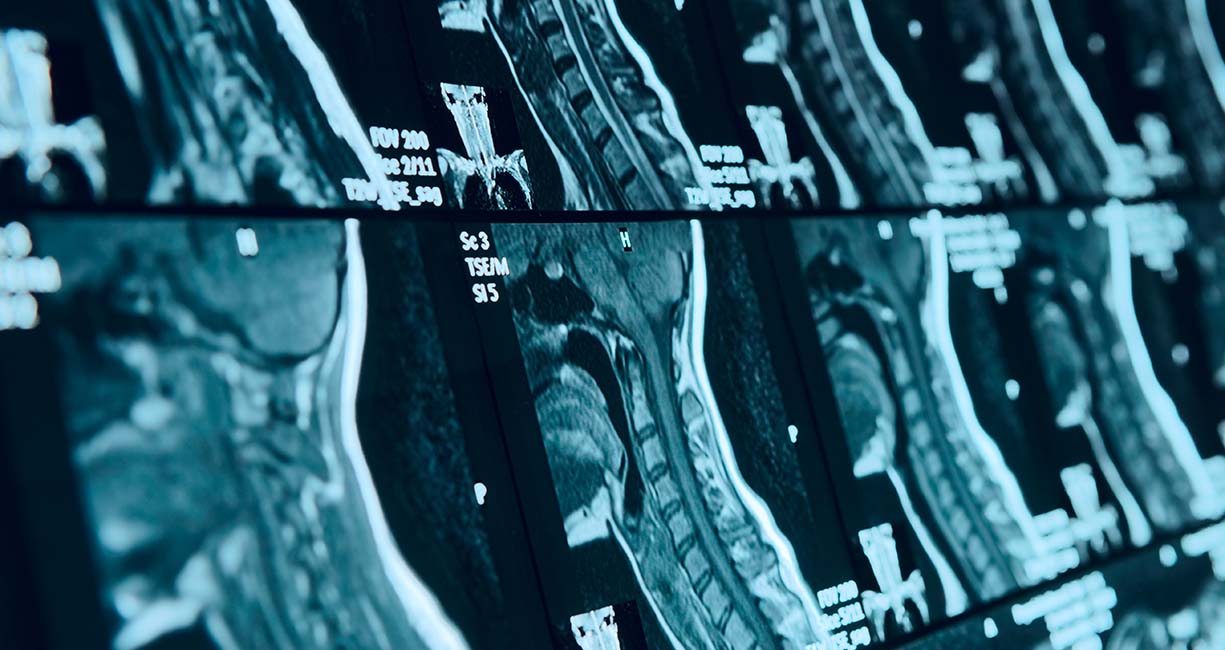

The sophistication of X-ray use and the advent of MRI and CAT scan technologies have added to so many of today’s successful practices and to the direct benefit of the patients we care for.

The evidence in the literature offers so much for a practitioner to learn that directly affects patient care. There is also emerging technology to diagnose biomechanical pathology more accurately, which is the core of what we treat. When considering an accurate clinical evaluation, motion palpation is a clinically sound starting point; however, static and motion palpation have poor intra- and inter-rater reliability outcomes.1-4 Once concluded in a thorough clinical evaluation, imaging should be considered to validate a dysfunctional vertebral motion segment. X-ray is a reliable tool to diagnose dysfunctional segments conclusively.5-9

In today’s marketplace, bringing a course for CE that is not based on a doctor’s experience or belief takes time, resources, a lot of research and often collaboration with he medical community. Being a CE provider for more than two decades has given me a front-row seat in the process. Similar to medicine, to educating doctors on being more accurate diagnostician requires those who are best at teaching. Those typically are in academia. When considering teaching stroke analysis and early diagnosis, we have no one in our profession with the knowledge or experience of a double-boarded vascular neurologist from a medical teaching institution. When teaching MRI spine interpretation, our DACBRs are incredibly smart, but do not have the same in-depth knowledge or experience as a neuroradiologist from Harvard who worked with Dr. Paul Lauterbur. (The Nobel Laureate who invented MRI and has been published more than 200 times, interpreted 1,000,000s of spinal MRIs and taught clinical rotations, residency programs, mini-fellowship and fellowship programs in medical and chiropractic academia.)